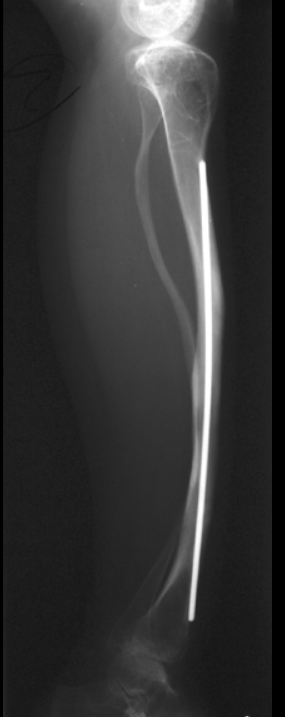

Long-bone stabilization device in OI.

Telescoping (extendable) rods.